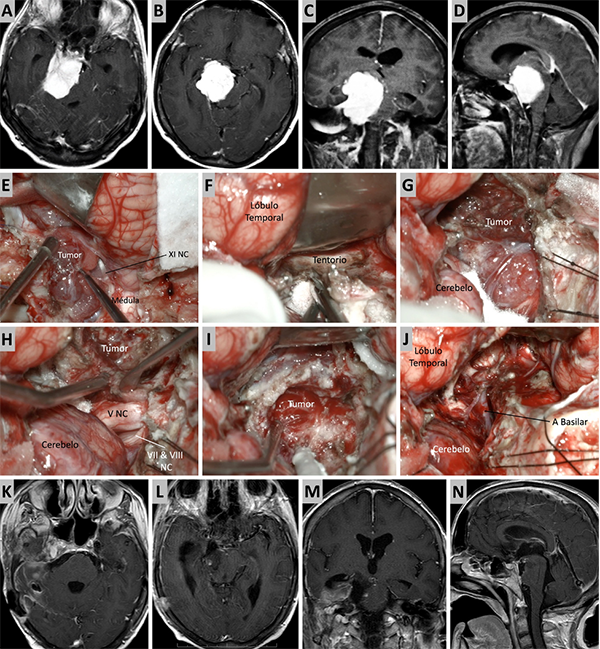

Figura 7. Caso ilustrativo #5. Resonancia que muestra MRPC con implantación petroclival y extensión a la fosa media. Paciente con audición conservada. A-D. Se presentan las imágenes prequirúrgicas, corte axial, coronal y sagital. E. Se realizo un abordaje presigmoideo combinado con un abordaje subtemporal. Se logro una visión directa del tumor, desde la región del clivus medio hasta la fosa media. F. Se observa una resección tumoral del clivus medio y fosa media casi total. G. Lesion tumoral en clivus medio. H-J. Resección casi total del tumor. La retracción del lóbulo temporal fue necesaria para tener mayor visibilidad de la incisura tentorial. K-N. RMN posquirúrgica donde se observa una resección quirúrgica casi total.